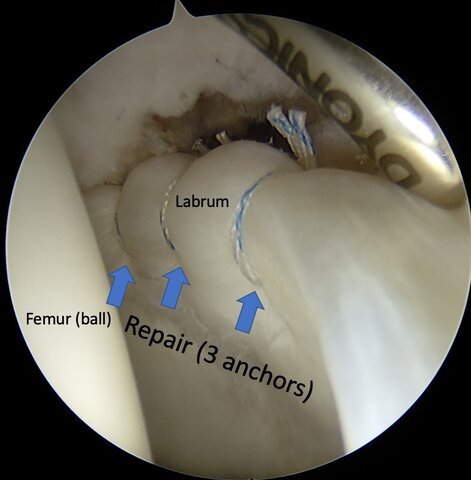

Surgery #1

I had my right labrum repaired and my hips broken and reformed (PAO).